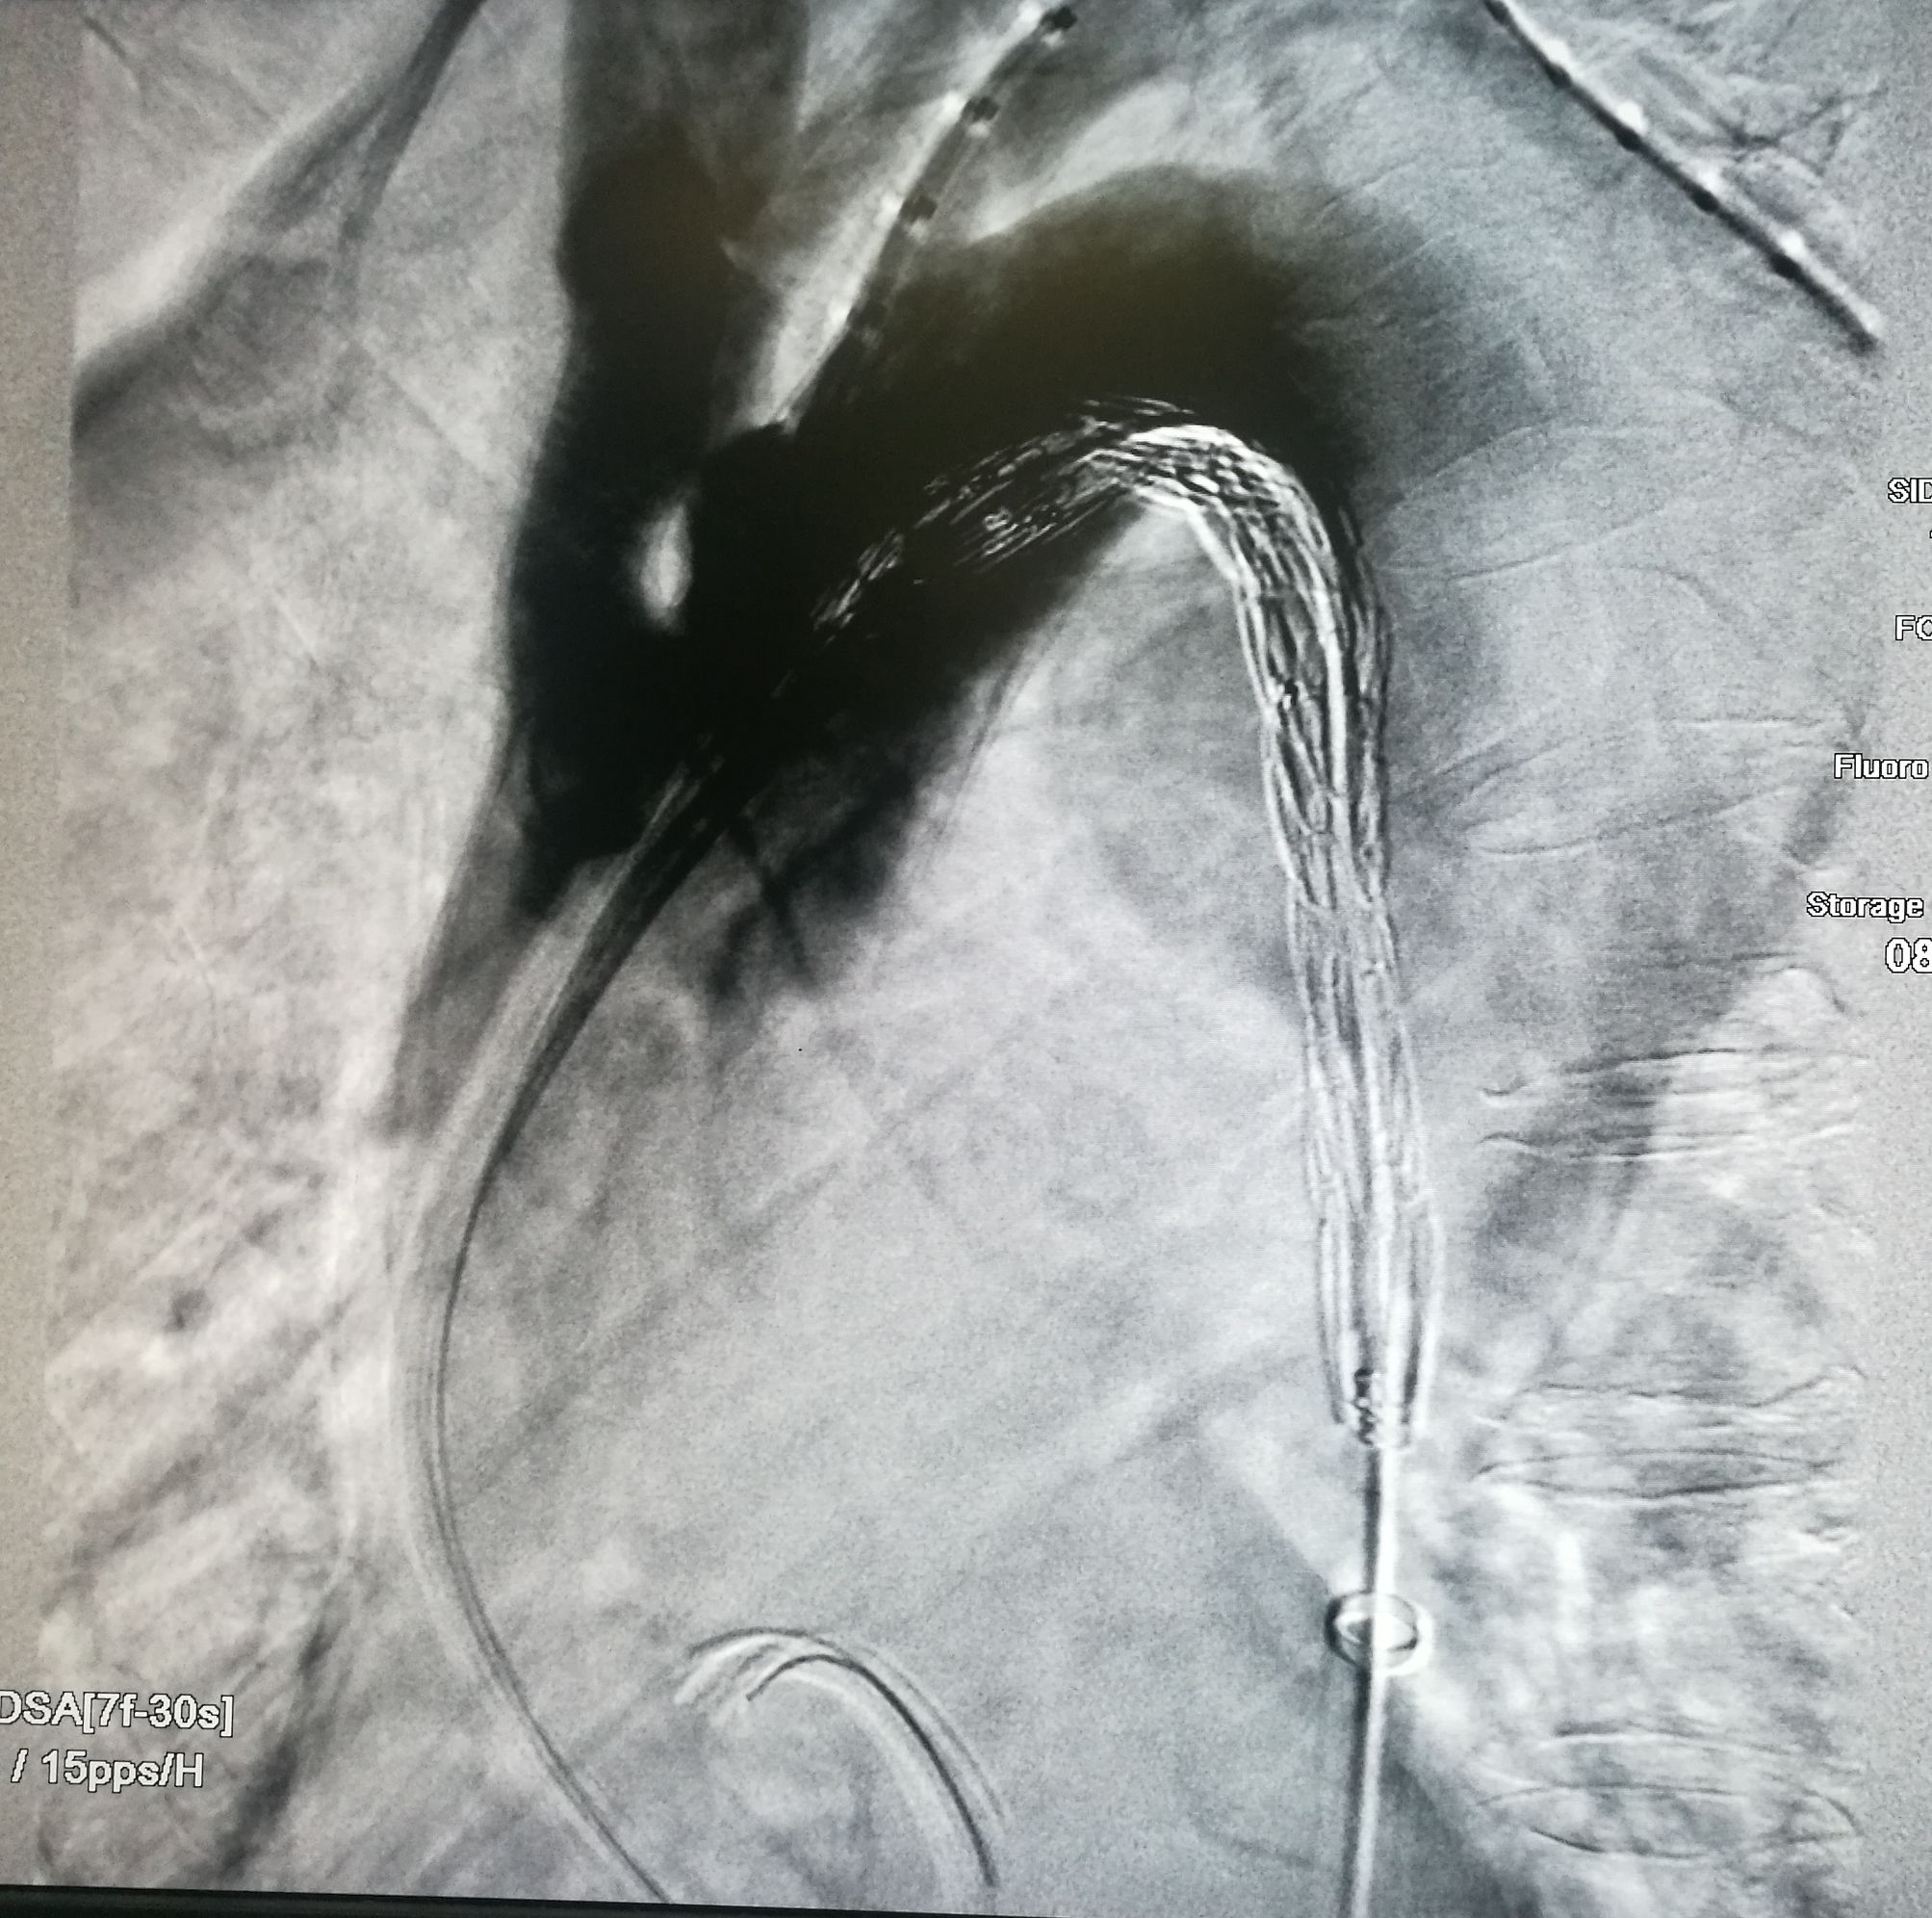

手术在局麻下进行,经右股动脉穿刺置管到升主,经左桡动脉穿刺植入金标猪尾导管,造影,为确认真假腔,加做右前斜位造影,确认股动脉导管在真腔内,测量后植入覆膜支架。由于扭曲严重(腹主,膈肌附近,弓降),支架最初并未贴服大湾侧,支架送过锁骨下动脉后适当回撤,请拉释放导丝,此时支架整体向大弯侧轻微移动,考虑应力已经得到缓解。完全释放支架,定位良好,封堵完全无内漏。

尽管有加硬导丝,但从二维影像上看,支架并未贴着大弯侧走行